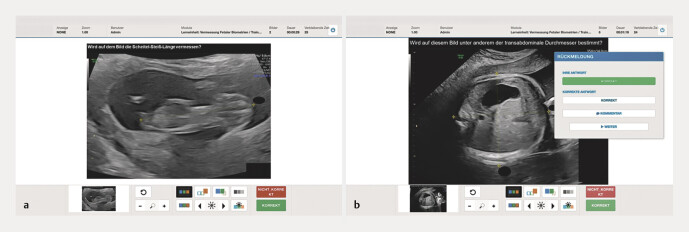

Methods: A prospective cross-sectional study was conducted with 76 medical students from the German University Hospital, divided into an intervention group (n = 37) and a control group (n = 39). The intervention group engaged with the AdaptUS module, which adjusts its content based on individual performance. More precisely, it is a learning program for ultrasound images that, while not directly adaptive to the user's skill level, can be considered adaptive in the sense that incorrectly answered images are presented again for re-interpretation. However, the images are currently shown at random and are not yet adjusted to the user's abilities, ensuring that the challenge is consistent but not tailored to skill level. It is important to note that this is not an ultrasound image software, but rather an image interpretation software designed to help users improve their diagnostic skills through repeated exposure to medical images. In contrast, the control group did not receive this training. Both groups were assessed on their ultrasound diagnostic skills at the beginning and end of the semester using a series of 16 questions, which involved interpreting images correctly rather than a standard multiple-choice format. Statistical analysis was performed to compare the pre- and post-test results within and between the groups.